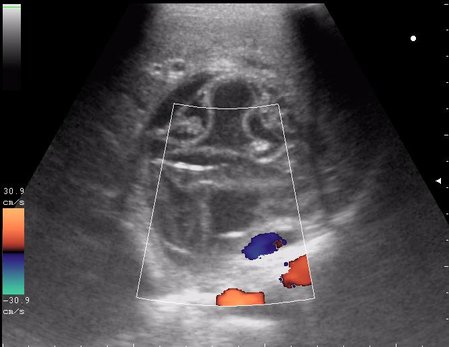

эхинококкоз печени девочка 12 лет.

живой эхинококк.